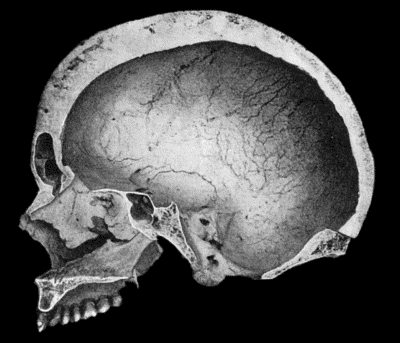

| 130. | Syphilitic Disease of Skull | 463 |

| 134. | Changes in the Skull resulting from Ostitis Deformans | 474 |